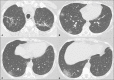

Objective: To describe the relationship between coronavirus disease 2019 (COVID-19) and pulmonary tuberculosis during the current pandemic, as well as to describe the main computed tomography (CT) findings in patients suffering from both diseases simultaneously.

Materials and methods: This was a retrospective, cross-sectional observational study of the chest CT scans of 360 patients with COVID-19, as confirmed by RT-PCR.

Results: In four (1.1%) of the patients, changes suggestive of COVID-19 and tuberculosis were observed on the initial CT scan of the chest. On chest CT scans performed for the follow-up of COVID-19, cavitary lesions with bronchogenic spread were observed in two of the four patients, whereas alterations consistent with the progression of fibrous scarring related to previous tuberculosis were observed in the two other patients. The diagnosis of tuberculosis was confirmed by the isolation of Mycobacterium tuberculosis.

Conclusion: Albeit rare, concomitant COVID-19 and tuberculosis can be suggested on the basis of the CT aspects. Radiologists should be aware of this possibility, because initial studies indicate that mortality rates are higher in patients suffering from both diseases simultaneously.